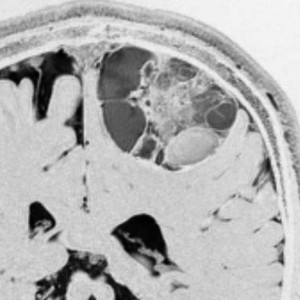

この例は,10歳の子どもに無症状で偶然発見された大きなのう胞性小脳毛様細胞性星細胞腫です。開頭手術で腫瘍結節は全摘出して腫瘍のう胞は縮小したままです。(画像はクリックすると拡大して見えます)

開頭手術で白く増強される結節部分だけを摘出しました。MIB-1はやや高値で3%と報告されました。病理組織診断は,WHO grade 1 毛様細胞性星細胞腫です。

6年後のMRI FLAIR画像です。摘出腔周囲の高信号域が残存しています。ここまで残ると腫瘍周辺浮腫ではありませんし,腫瘍細胞が左小脳半球に広範囲に浸潤して残存しているものだと判断されます。しかし,6年間で病変の増大傾向がありませんでした。この残存腫瘍(らしい所見)に対して放射線治療や化学療法を行うべきかどうか,結論は出ていません。しかし,経過観察を続けても増大して来ない例があることは確かです。一方で,この高信号領域が拡大したり,ガドリニウム増強される病変が再出現して治療がまた必用となることもあります。